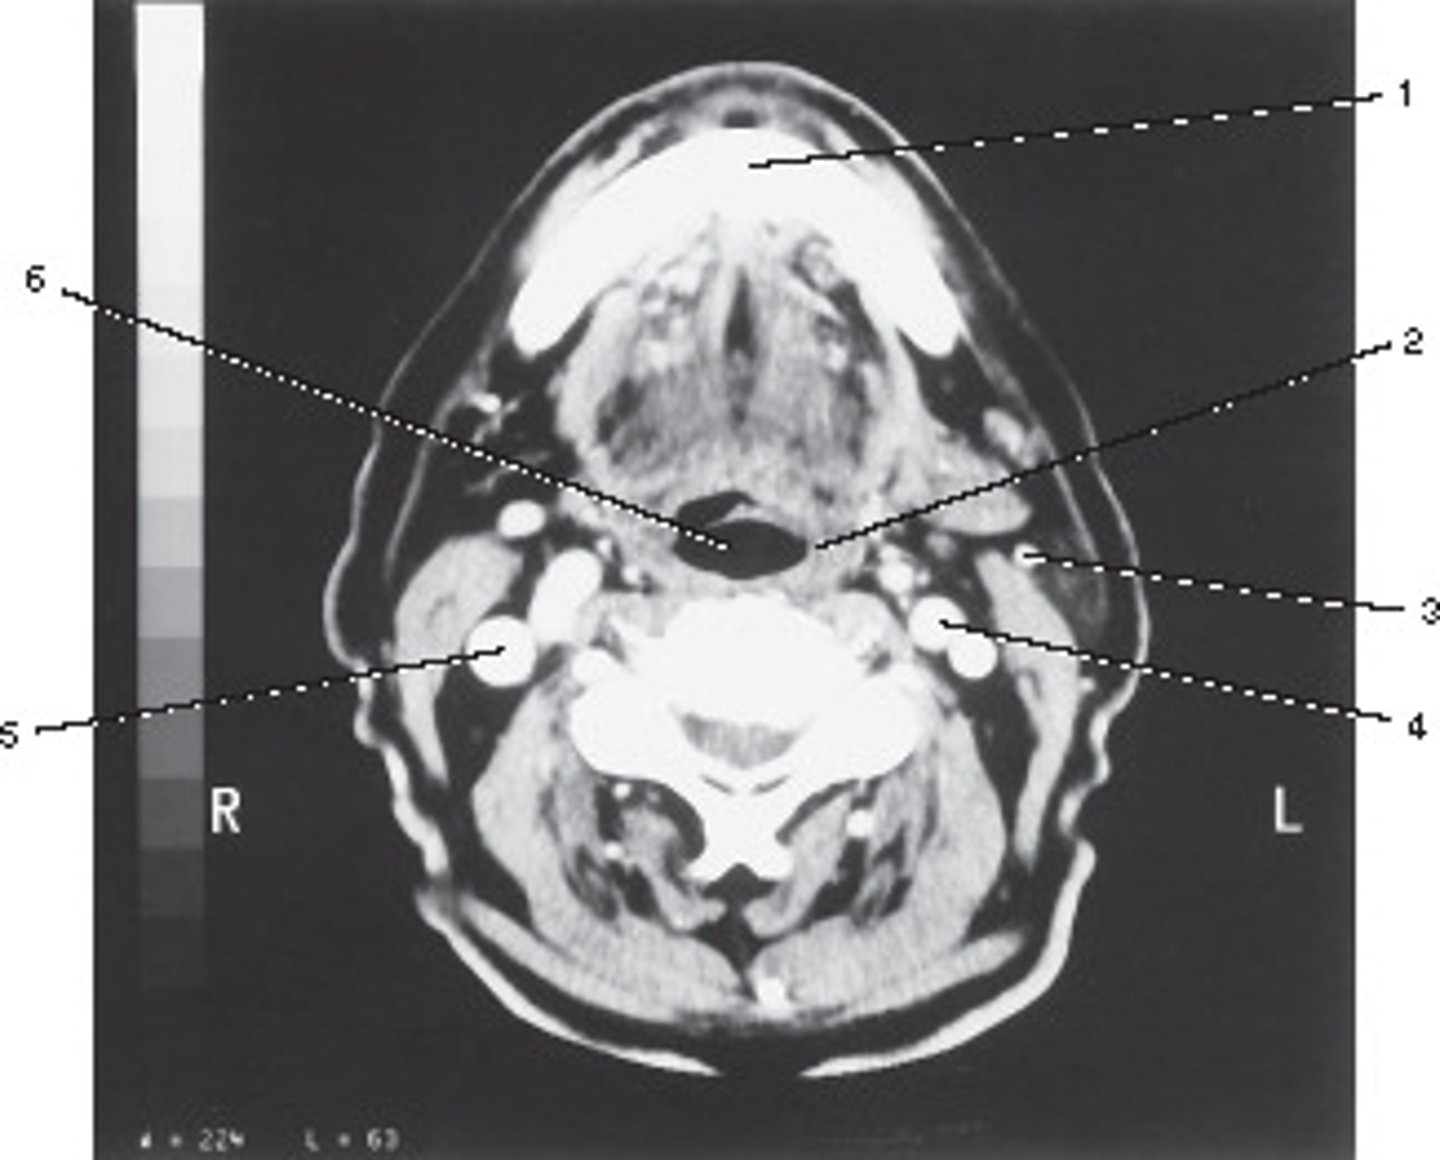

Oropharynx

Number 6 corresponds to which of the following?

<p>Number 6 corresponds to which of the following?</p>

Common Carotid Artery

Number 5 corresponds to which of the following?

<p>Number 5 corresponds to which of the following?</p>

Retromandibular Vein

Number 3 corresponds to which of the following?

<p>Number 3 corresponds to which of the following?</p>

Roots of the Teeth

Number 2 corresponds to which of the following?

<p>Number 2 corresponds to which of the following?</p>

Vertebral Artery